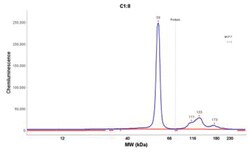

Cytokeratin 8 Monoclonal specifically detects Cytokeratin 8 in Human, Rat (Negative) samples. It is validated for Western Blot, Simple Western, Flow Cytometry, Immunohistochemistry, Immunocytochemistry/Immunofluorescence, Immunohistochemistry-Paraffin.Specifications

| 52.5 kDa |

| Epitope of this MAb is located between aa343-357. Cytokeratin 8 (CK8) belongs to the type II (or B or basic) subfamily of high molecular weight cytokeratins and exists in combination with cytokeratin 18 (CK18). CK8 is primarily found in the non-squamous epithelia and is present in majority of adenocarcinomas and ductal carcinomas. It is absent in squamous cell carcinomas. Hepatocellular carcinomas are defined by the use of antibodies that recognize only cytokeratin 8 and 18. CK8 exists on several types of normal and neoplastic epithelia, including many ductal and glandular epithelia such as colon, stomach, small intestine, trachea, and esophagus as well as in transitional epithelium. Anti-CK8 does not react with skeletal muscle or nerve cells. Epithelioid sarcoma, chordoma, and adamantinoma show strong positivity corresponding to that of simple epithelia (with antibodies against CK8, CK18 and CK19). Reportedly, anti-CK8 is useful for the differentiation of lobular (ring-like, perinuclear) from ductal (peripheral-predominant) carcinoma of the breast. |